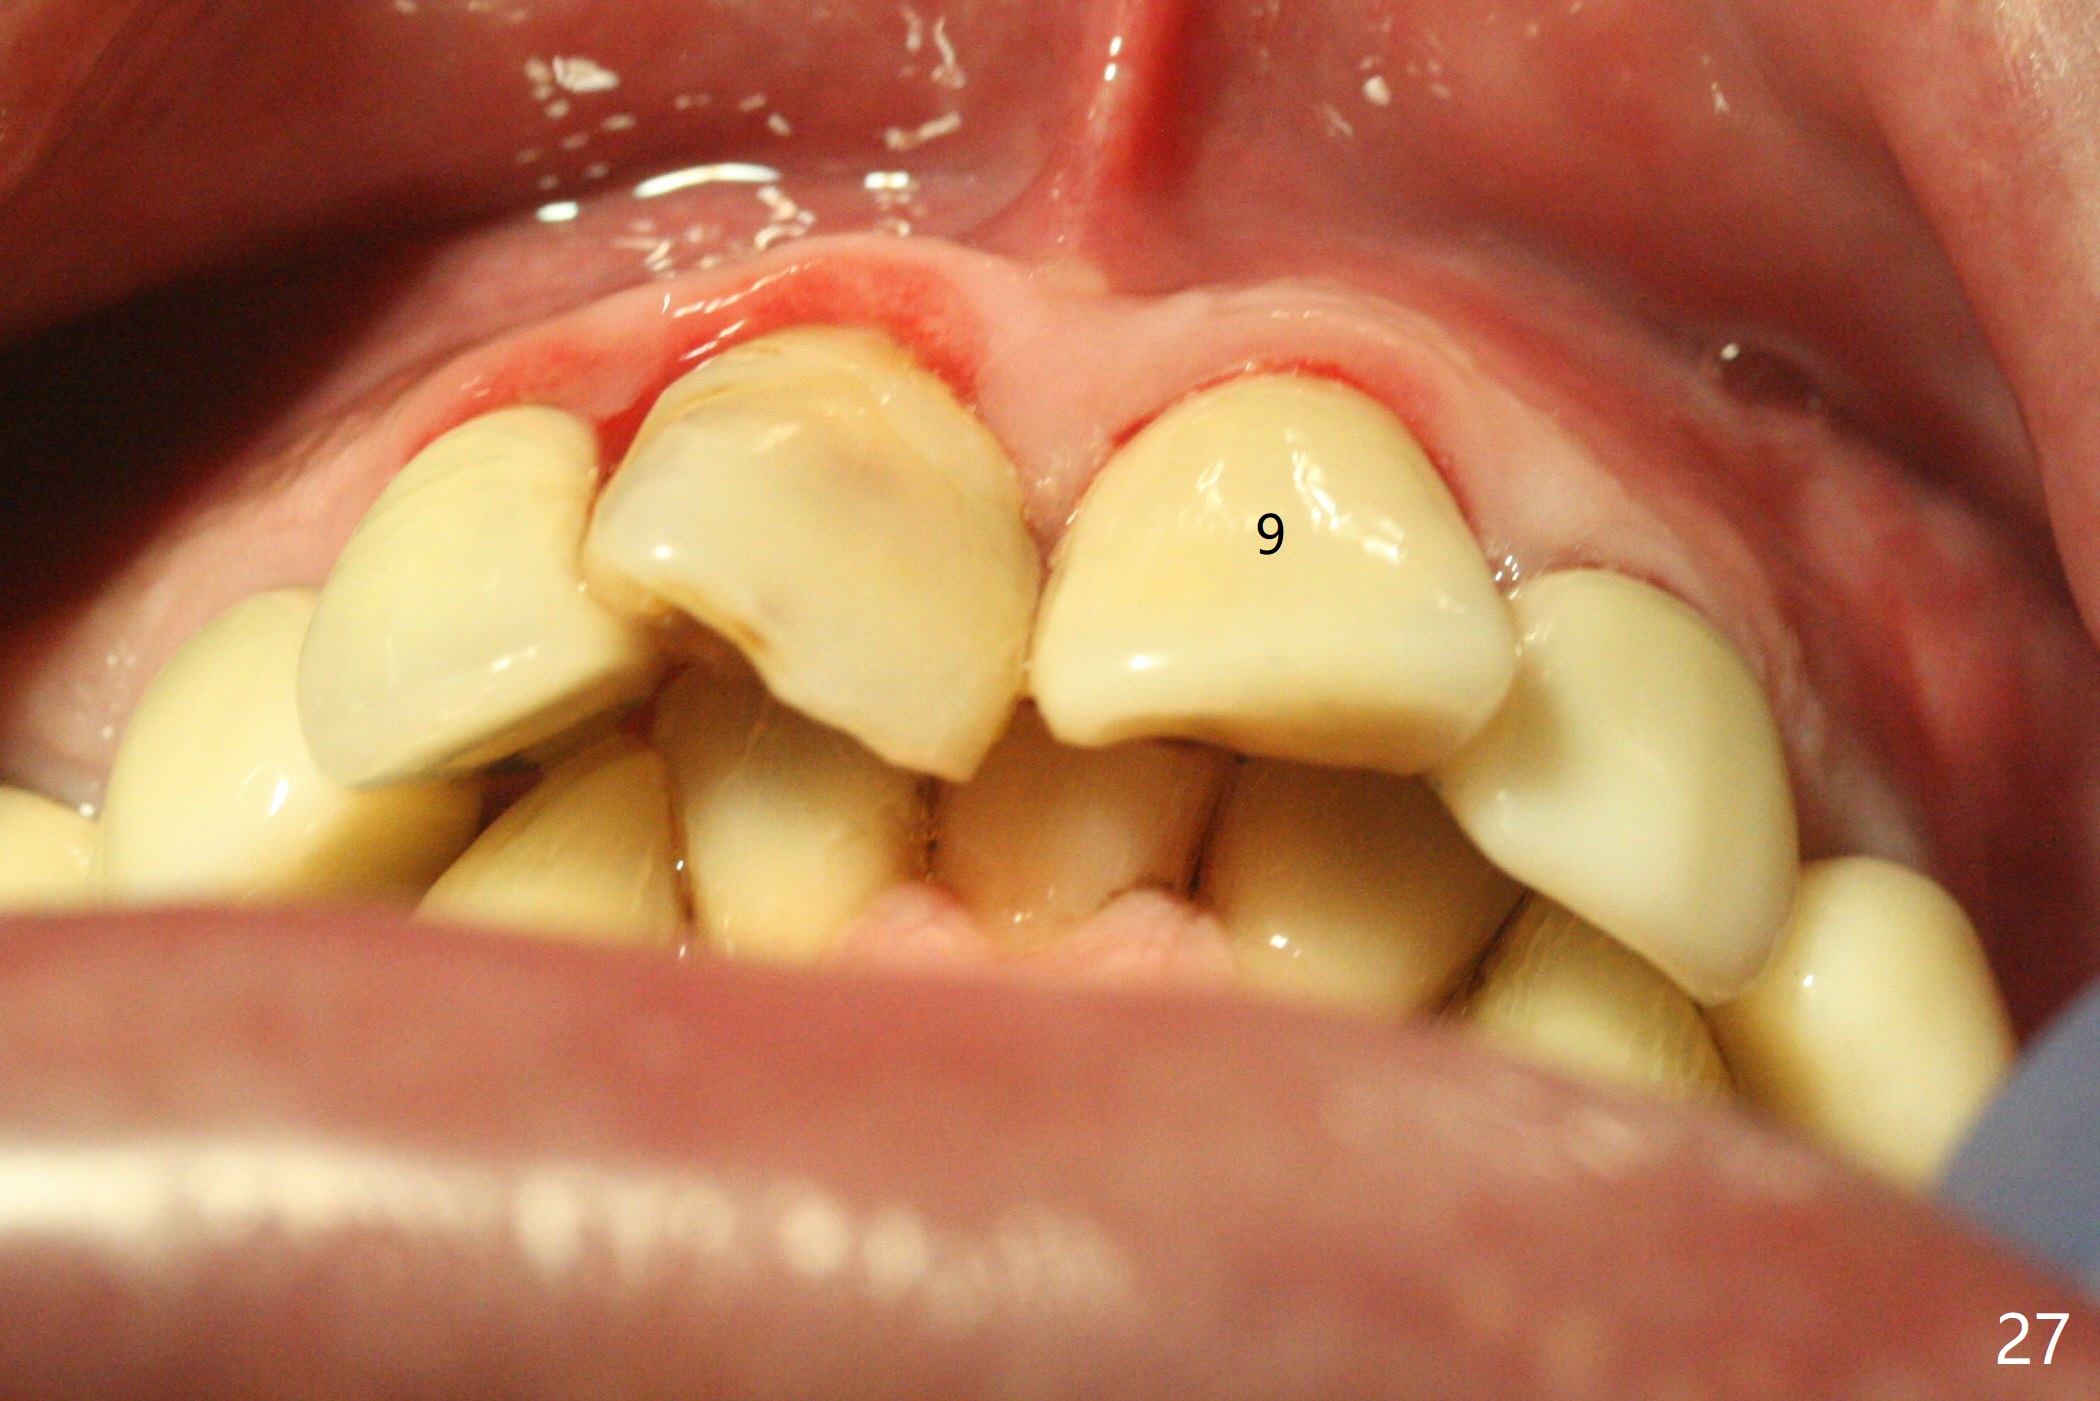

Six months post cementation, the tooth #9 becomes symptomatic.  Is it possible that the implant at #10 is too close to the root of #9?  It is asymptomatic after pulpotomy, but the tooth fractures equi/supragingivally.  Two PAs taken while RCT show osteointegration at #10-12 (Fig.18,19).  While the bone density increases at #10 regular implant, there is minimal bone loss around the 1-piece implants 13 months post cementation (18 months postop, Fig.20,21).  The gingiva remains healthy 19 months post cementation (Fig.22).  76岁病人突然打电话说一个植牙牙冠松动,其实9号牙(自然牙)折裂,6,10-13号牙植牙好像没有骨质吸收(图二十三至二十五),10-13牙位牙龈健康(图二十六,行使功能五年)。9号牙牙冠重新粘固后,显示前牙深覆合,深覆盖(图二十七,二十八)。如果再次脱落需要植牙,选择一段式有助于植入和修复,因为植体和基台直径小。两段式植牙相对基台直径至少4,或者4.5毫米,前牙修复显得笨重。由于9,10牙根和植体接近,9号牙植体需要偏小而长,3x14或者15毫米(图二十九)。